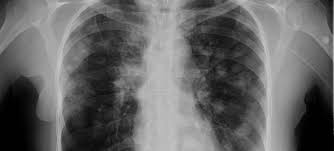

Signs Of Breast Cancer Recurrence In Lungs - P66shca Functions As A Contextual Promoter Of Breast Cancer Metastasis Breast Cancer Research Full Text - More generalized symptoms of cancer, such as fatigue and unintentional weight loss, may also signal a recurrence.. Breast cancer can come back as a local recurrence (in the treated breast or near the mastectomy scar) or as a distant recurrence somewhere else in the body.the most common sites of recurrence include the lymph nodes, the bones, liver, or lungs. When breast cancer moves into the lung, it often doesn't cause symptoms. It can also return and spread to other parts of the body (called metastasis or distant recurrence). Metastatic breast cancer after treatment for early or locally advanced breast cancer (stages i, ii and iii), it's possible for breast cancer to return (recur) and spread to other parts of the body (metastasize). Many of them share symptoms.

Local recurrence is usually found on a mammogram, during a physical exam by a health care provider or when you notice a change in or around the breast or underarm. Many of them share symptoms. Distant recurrence occurs when breast cancer returns in areas further away from the initial site, such as the bones, the lungs, or the brain. Metastatic breast cancer is cancer that's spread from the breasts. The most common sites for breast cancer to spread are the brain, lung, liver and/or.

These are the locations where the recurrence is most often diagnosed. If your breast cancer has metastasized to your lungs, you may not notice any symptoms right away. Symptoms and diagnosis when breast cancer moves into the lung, it often doesn't cause symptoms. If cancer cells are blocking the lymph nodes in. Cancer that comes back after treatment is called a recurrence.but some cancer survivors develop a new, unrelated cancer later. This is the most common type of breast cancer.it begins in. Each person's risk of breast cancer recurrence is different and depends on many factors, such as the size, type, grade and features of the cancer and whether the lymph nodes were affected. Pain or discomfort in the lung This recurrence is also known as metastatic recurrence and cancer travels to the far places in the body like bones, lungs and sometimes even to liver. Pain in your bones, which may get worse when lying down; Symptoms of metastatic breast cancer in the. It causes pain in the bone and chest, continuous dry cough, loss of appetite, nausea and vomiting with severe headaches and fever with chills. Distant recurrence a distant (metastatic) recurrence means the cancer has traveled to distant parts of the body, most commonly the bones, liver and lungs.

The symptoms of a local cancer recurrence are specific to the original cancer. Symptoms and diagnosis when breast cancer moves into the lung, it often doesn't cause symptoms. Download a quick guide to the signs and symptoms of secondary breast cancer. It can also return and spread to other parts of the body (called metastasis or distant recurrence). Breast cancer tends to metastasize preferentially to the bone, lung, liver, spine and larger bones, brain, in that order of prevalence.

Stage 4 Breast Cancer Symptoms And Prognosis from post.medicalnewstoday.com As we see in ms. Breast cancer that comes back in the lymph nodes in the armpit, close to the breast bone, or lower neck, is called a regional recurrence. If a lung metastasis does cause symptoms, they may include: The most common sites for breast cancer to spread are the brain, lung, liver and/or. With breast cancer, these warning signs can include a new lump in the breast or changes to the surrounding skin. If symptoms do appear, they can resemble those of a cold or flu. It causes pain in the bone and chest, continuous dry cough, loss of appetite, nausea and vomiting with severe headaches and fever with chills. Local recurrence is usually found on a mammogram, during a physical exam by a health care provider or when you notice a change in or around the breast or underarm.